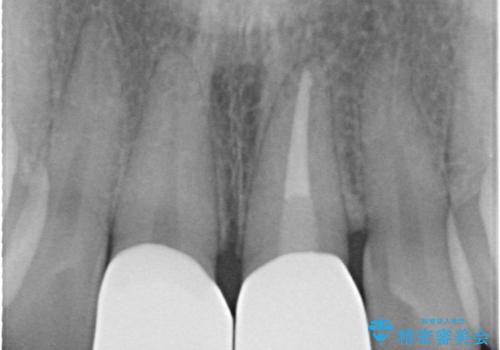

左上の前歯がわずかに短いことを気にされていたため、歯周外科にてこれを可及的に改善し、セラミックにて修復を行いました。

セラミックの種類:PFZ standard

今回は、仮歯の状態で歯の長さを調整する歯周外科をおこなう

→歯茎の治りを待っている間、根管治療のやり直しを行う

→土台を築造しセラミックを完成させる

ことで前歯を残し、長さが揃うようにしました。